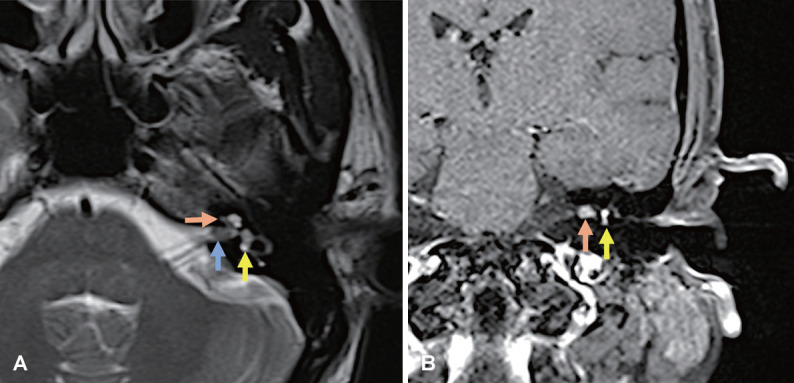

Intralabyrinthine schwannomas (ILSs) are rare tumors involving the otic capsule. Notably, they are often misdiagnosed because their symptoms mimic those of other, more common inner ear pathologies. Diagnosis requires high-resolution contrast-enhanced magnetic resonance imaging (MRI), which reveals filling defects (using a T2-weighted MRI sequence) or focal enhancement (using a T1-weighted MRI sequence with gadolinium enhancement) in the inner ear. A 52-year-old male patient with intractable vertigo or single-sided deafness should raise suspicion of this clinical entity as a differential diagnosis. Translabyrinthine excision of the tumor along with auditory rehabilitation using a cochlear implant can provide good outcomes with minimal morbidity in carefully selected cases. Here, we present an interesting case of a transmodiolar ILS mimicking Meniere's disease, wherein surgery using the translabyrinthine approach and an extended cochleostomy yielded favorable outcomes.